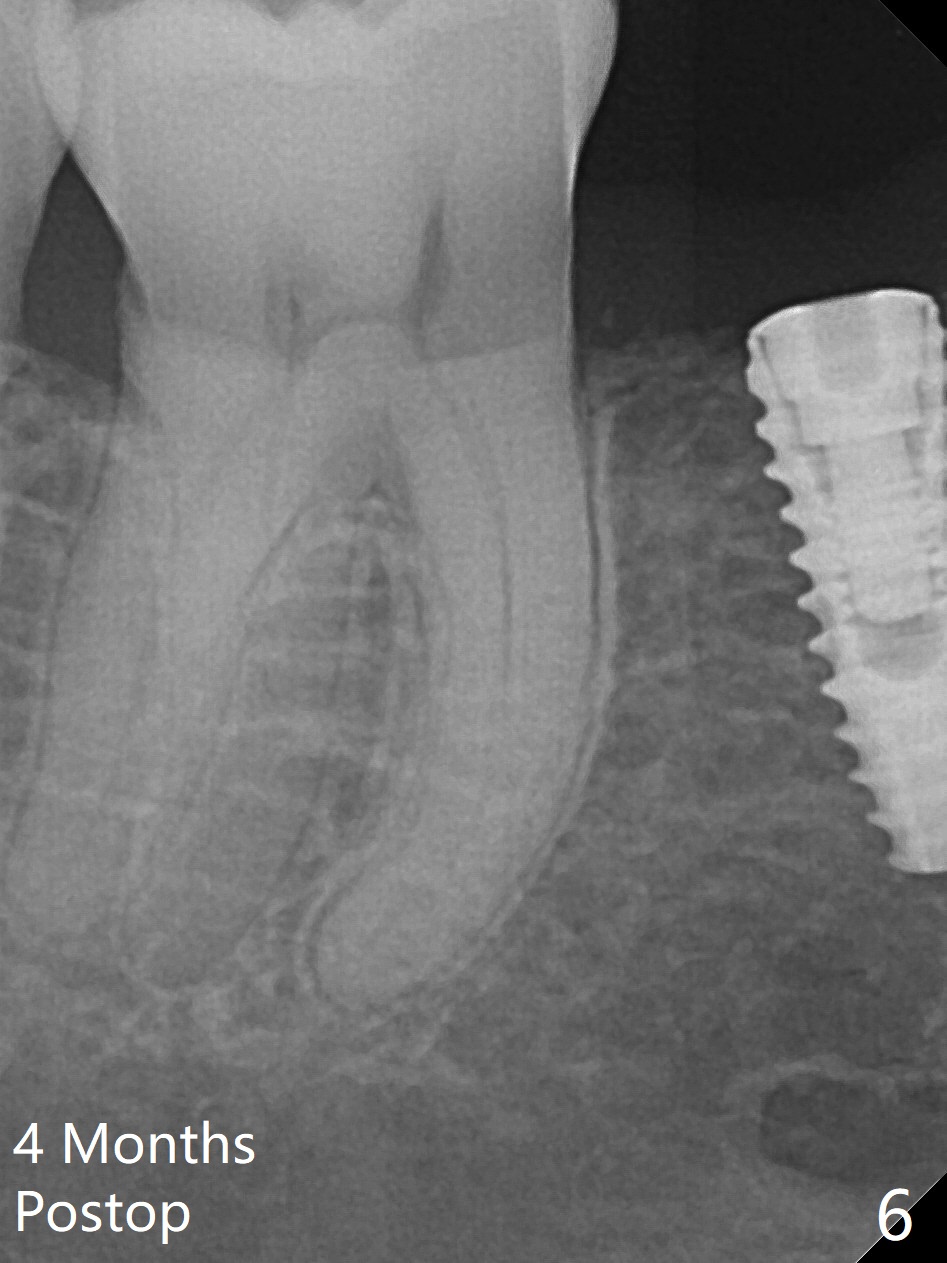

After incision the ridge at #29 is not so narrow as shown in Fig.1. But it is still intact, in contrast to what CBCT shows. Osteotomy is initiated with 1.2 mm drill, followed by 1/1.6, 1.3/2.3 and 1.7/3.1 mm DIO Bone Expanders. In fact mesial and distal crestal slots (BEB: bone expansion and bending) are created by using surgical fissure bur in order to insert the last bone expander in place (10 mm, Fig.2). Following 3.5 mm Cortical Tap, a 3.5x10 mm IS Implant is placed ~ 50 Ncm with clearance from the Mental Loop (Fig.3,4 red dashed line) and slightly subcrestal (Fig.5). The most distal part of the distal slot created for BEB is shown in Fig.5 *. Bone resorption is minimal 4 months postop (Fig.6,7). The implant was apparently placed in the middle buccolingually (Fig.8).